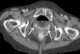

Carcinoma of vagina

Squamous-cell carcinoma of the vagina is a potentially invasive type of cancer that forms in the tissues of the vagina. Though uncommon, squamous-cell cancer of the vagina (SCCV) is the most common type of vaginal cancer. [Source: Wikipedia ]